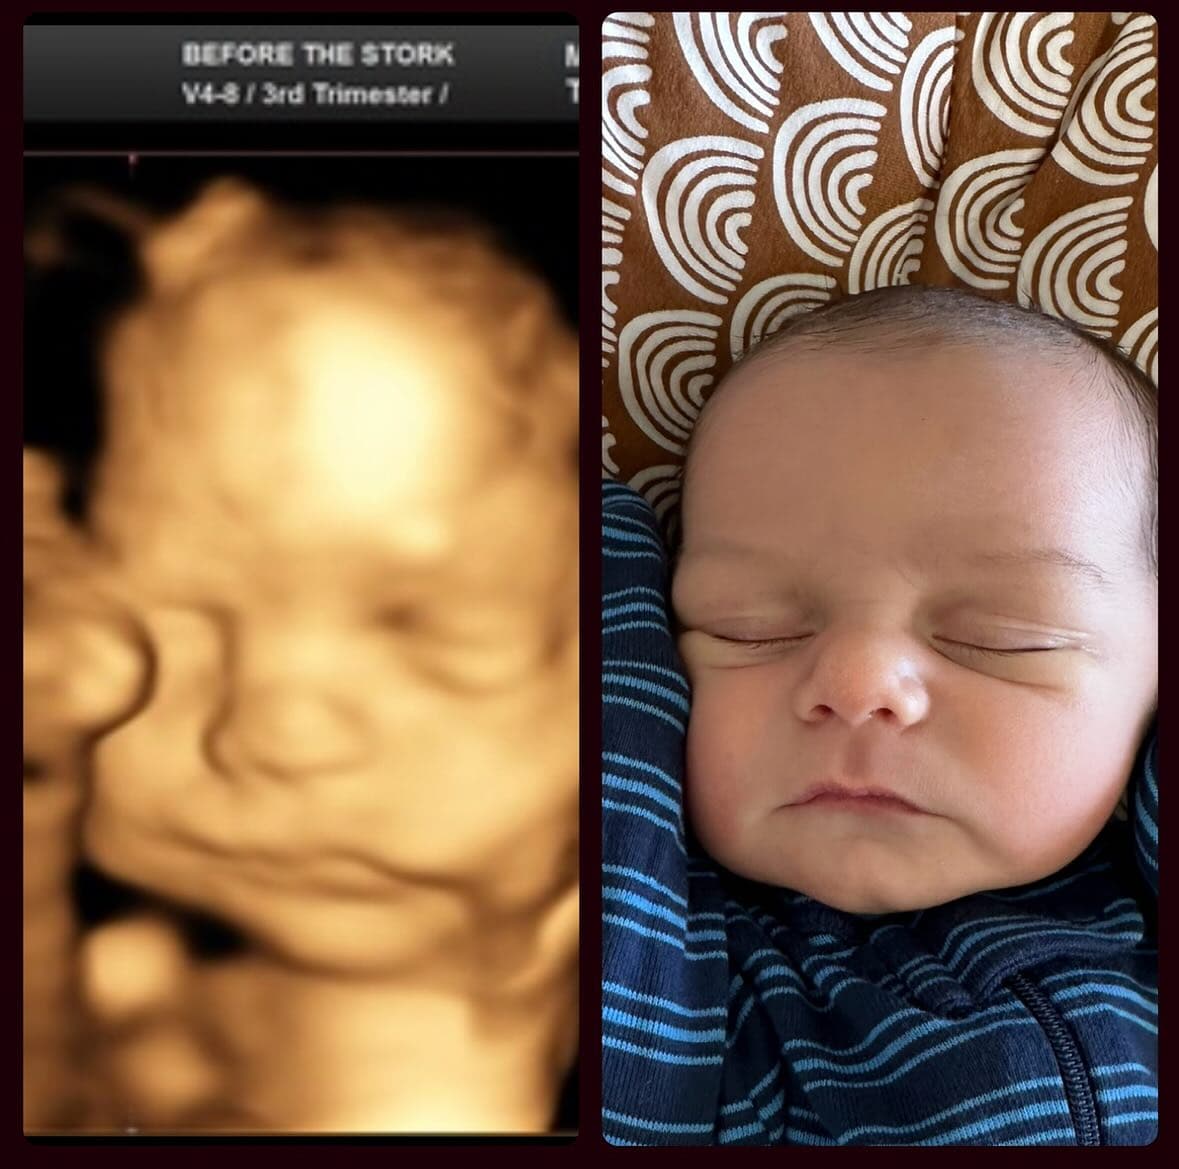

What Parents Actually Experience

The most common reaction after birth? "The nose looks nothing like the ultrasound." Pregnancy forums are full of parents sharing their 3D ultrasound next to their newborn photo, and the difference is striking. Wide, flat ultrasound noses turn into perfectly normal (often tiny) baby noses.

Ultrasound studios publish before-and-after galleries showing 3D scans alongside the born baby—and you can see the pattern clearly: the nose is almost always wider on the scan. Browse real examples at Fetal Vision Imaging, 3D Baby Boutique, and Baby Moments Ultrasound. Not every case is dramatic—some noses match closely—but the wide-nose effect is by far the most common outcome.

This makes sense when you understand what a 3D ultrasound actually is: a surface rendering built from sound waves, not a photograph. It captures general shape but distorts proportions, especially for protruding features like the nose.